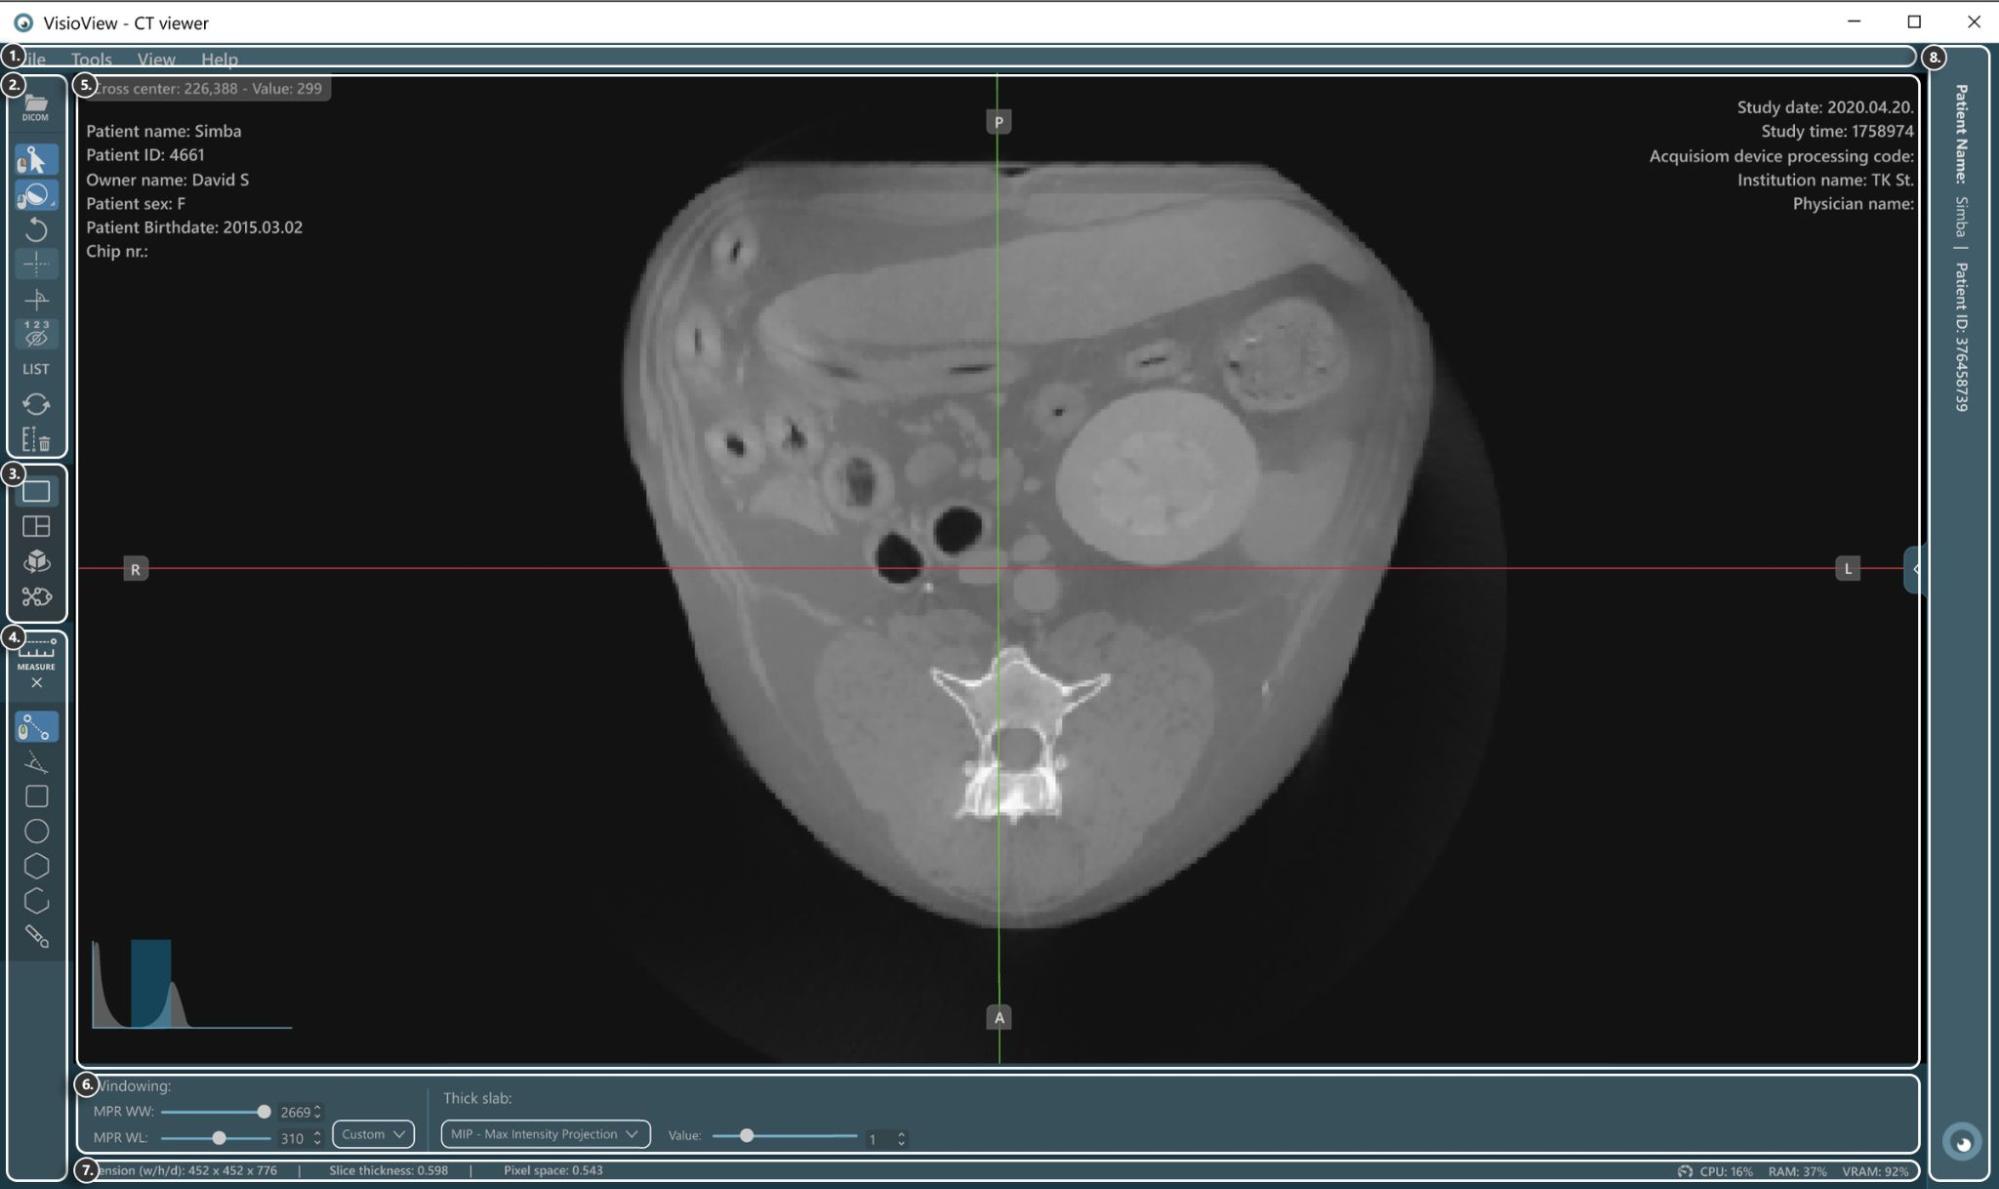

Sections of the VisioVIEW CT Viewer¶

The VisioVIEW CT Viewer consists of several sections, each tailored to a specific purpose. Below is a detailed description of each section.

Viewer Area¶

HU (Hounsfield Unit) pixel value

Patient information

Windowing histogram tool

Slicers

Study information

View Settings and Options¶

Windowing settings

Thick slab settings

Information Bar¶

DICOM image and resolution information

Performance and resource usage information